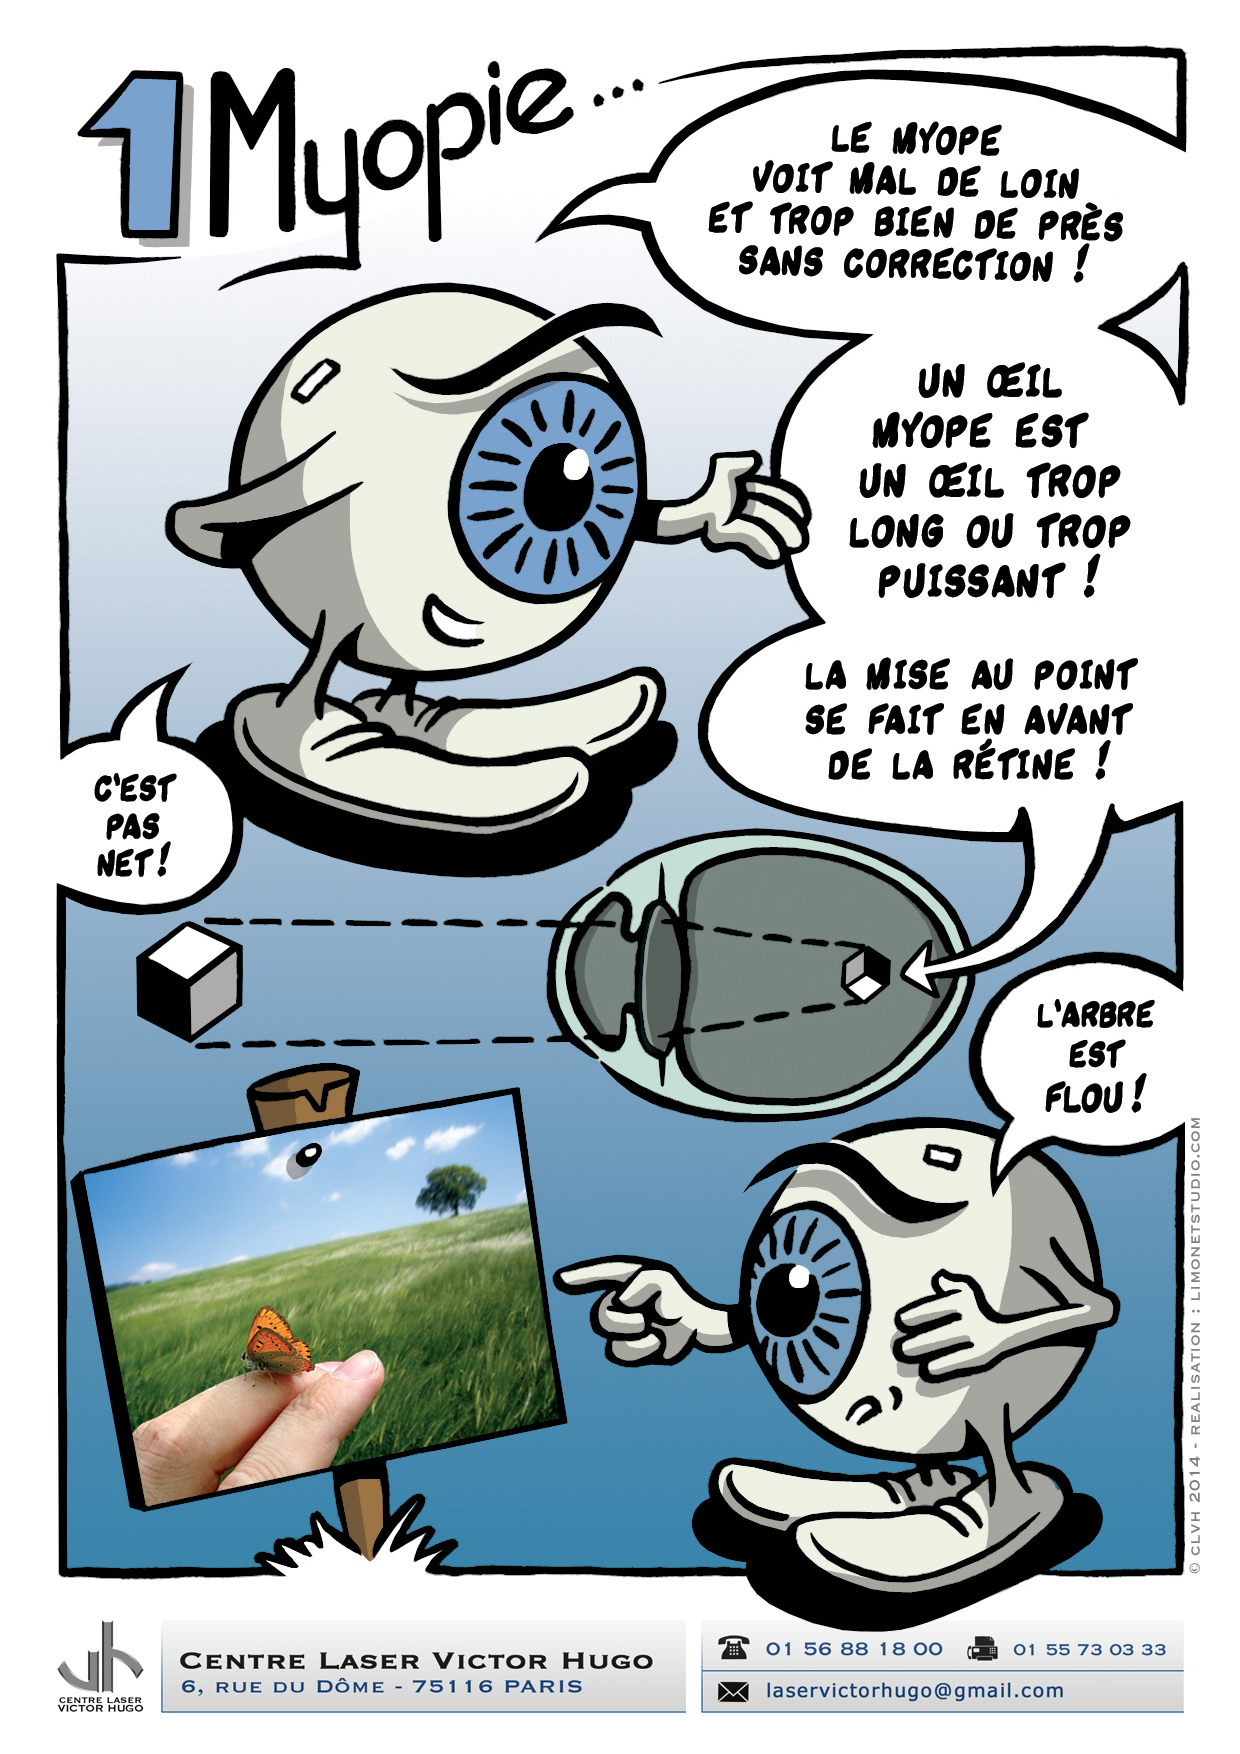

Afin de répondre aux interrogations d'un public de plus en plus intéressé, nous vous proposons cet ouvrage explicatif sous la forme d'une bande dessinée ludique. Cette bédé aborde les troubles de la vision, la chirurgie réfractive (LASIK, PKR et PresbyLASIK), la technique des anneaux et des implants. Cette bébé aborde également l'amblyopie et son traitement orthoptique. Maintenant... à vous de voir !